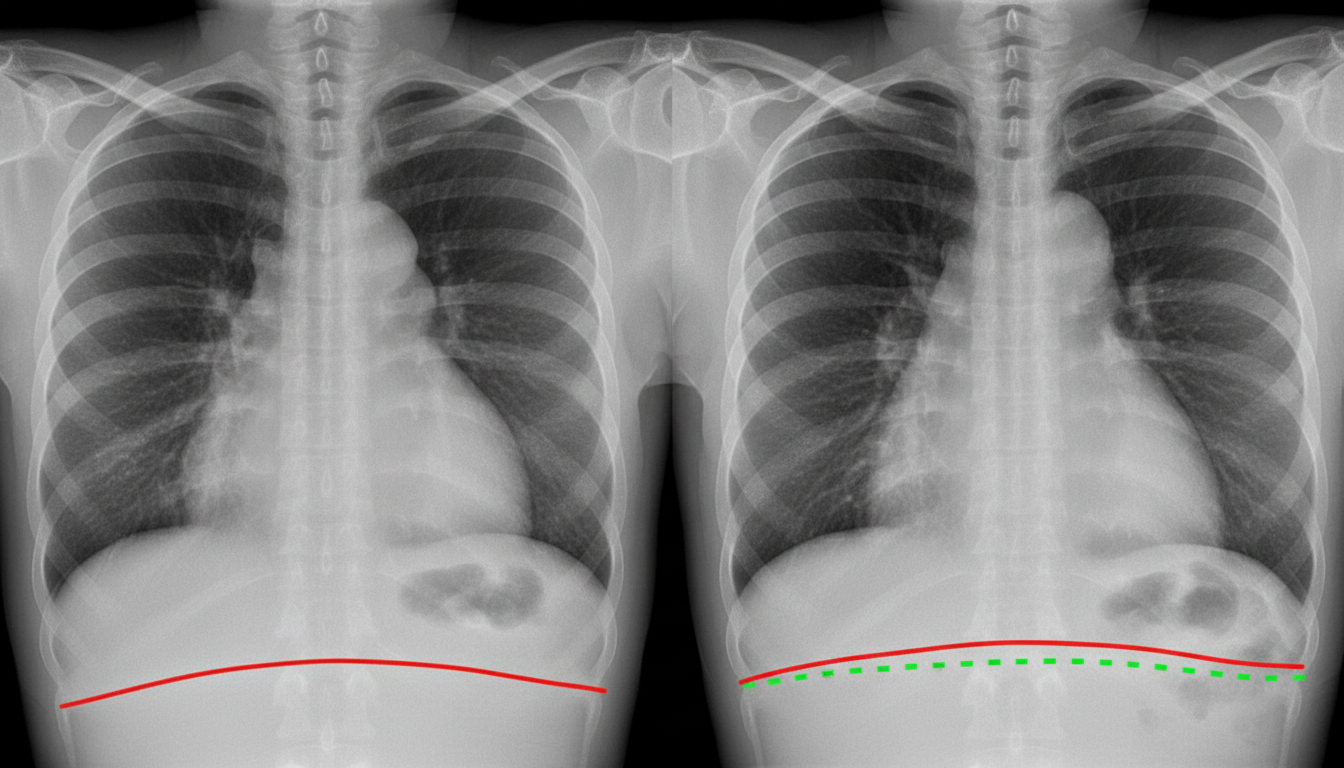

Clinical Patterns - Obstructive vs. Restrictive

- Obstructive: Difficulty exhaling air due to increased airway resistance. Think "Outflow" problem.

- Restrictive: Difficulty expanding lungs, leading to reduced lung volumes. Think "Inflow" problem.

| Total Lung Capacity (TLC) | Normal or ↑ | ↓↓ |

- In obstructive diseases, TLC and RV are ↑ due to air trapping.